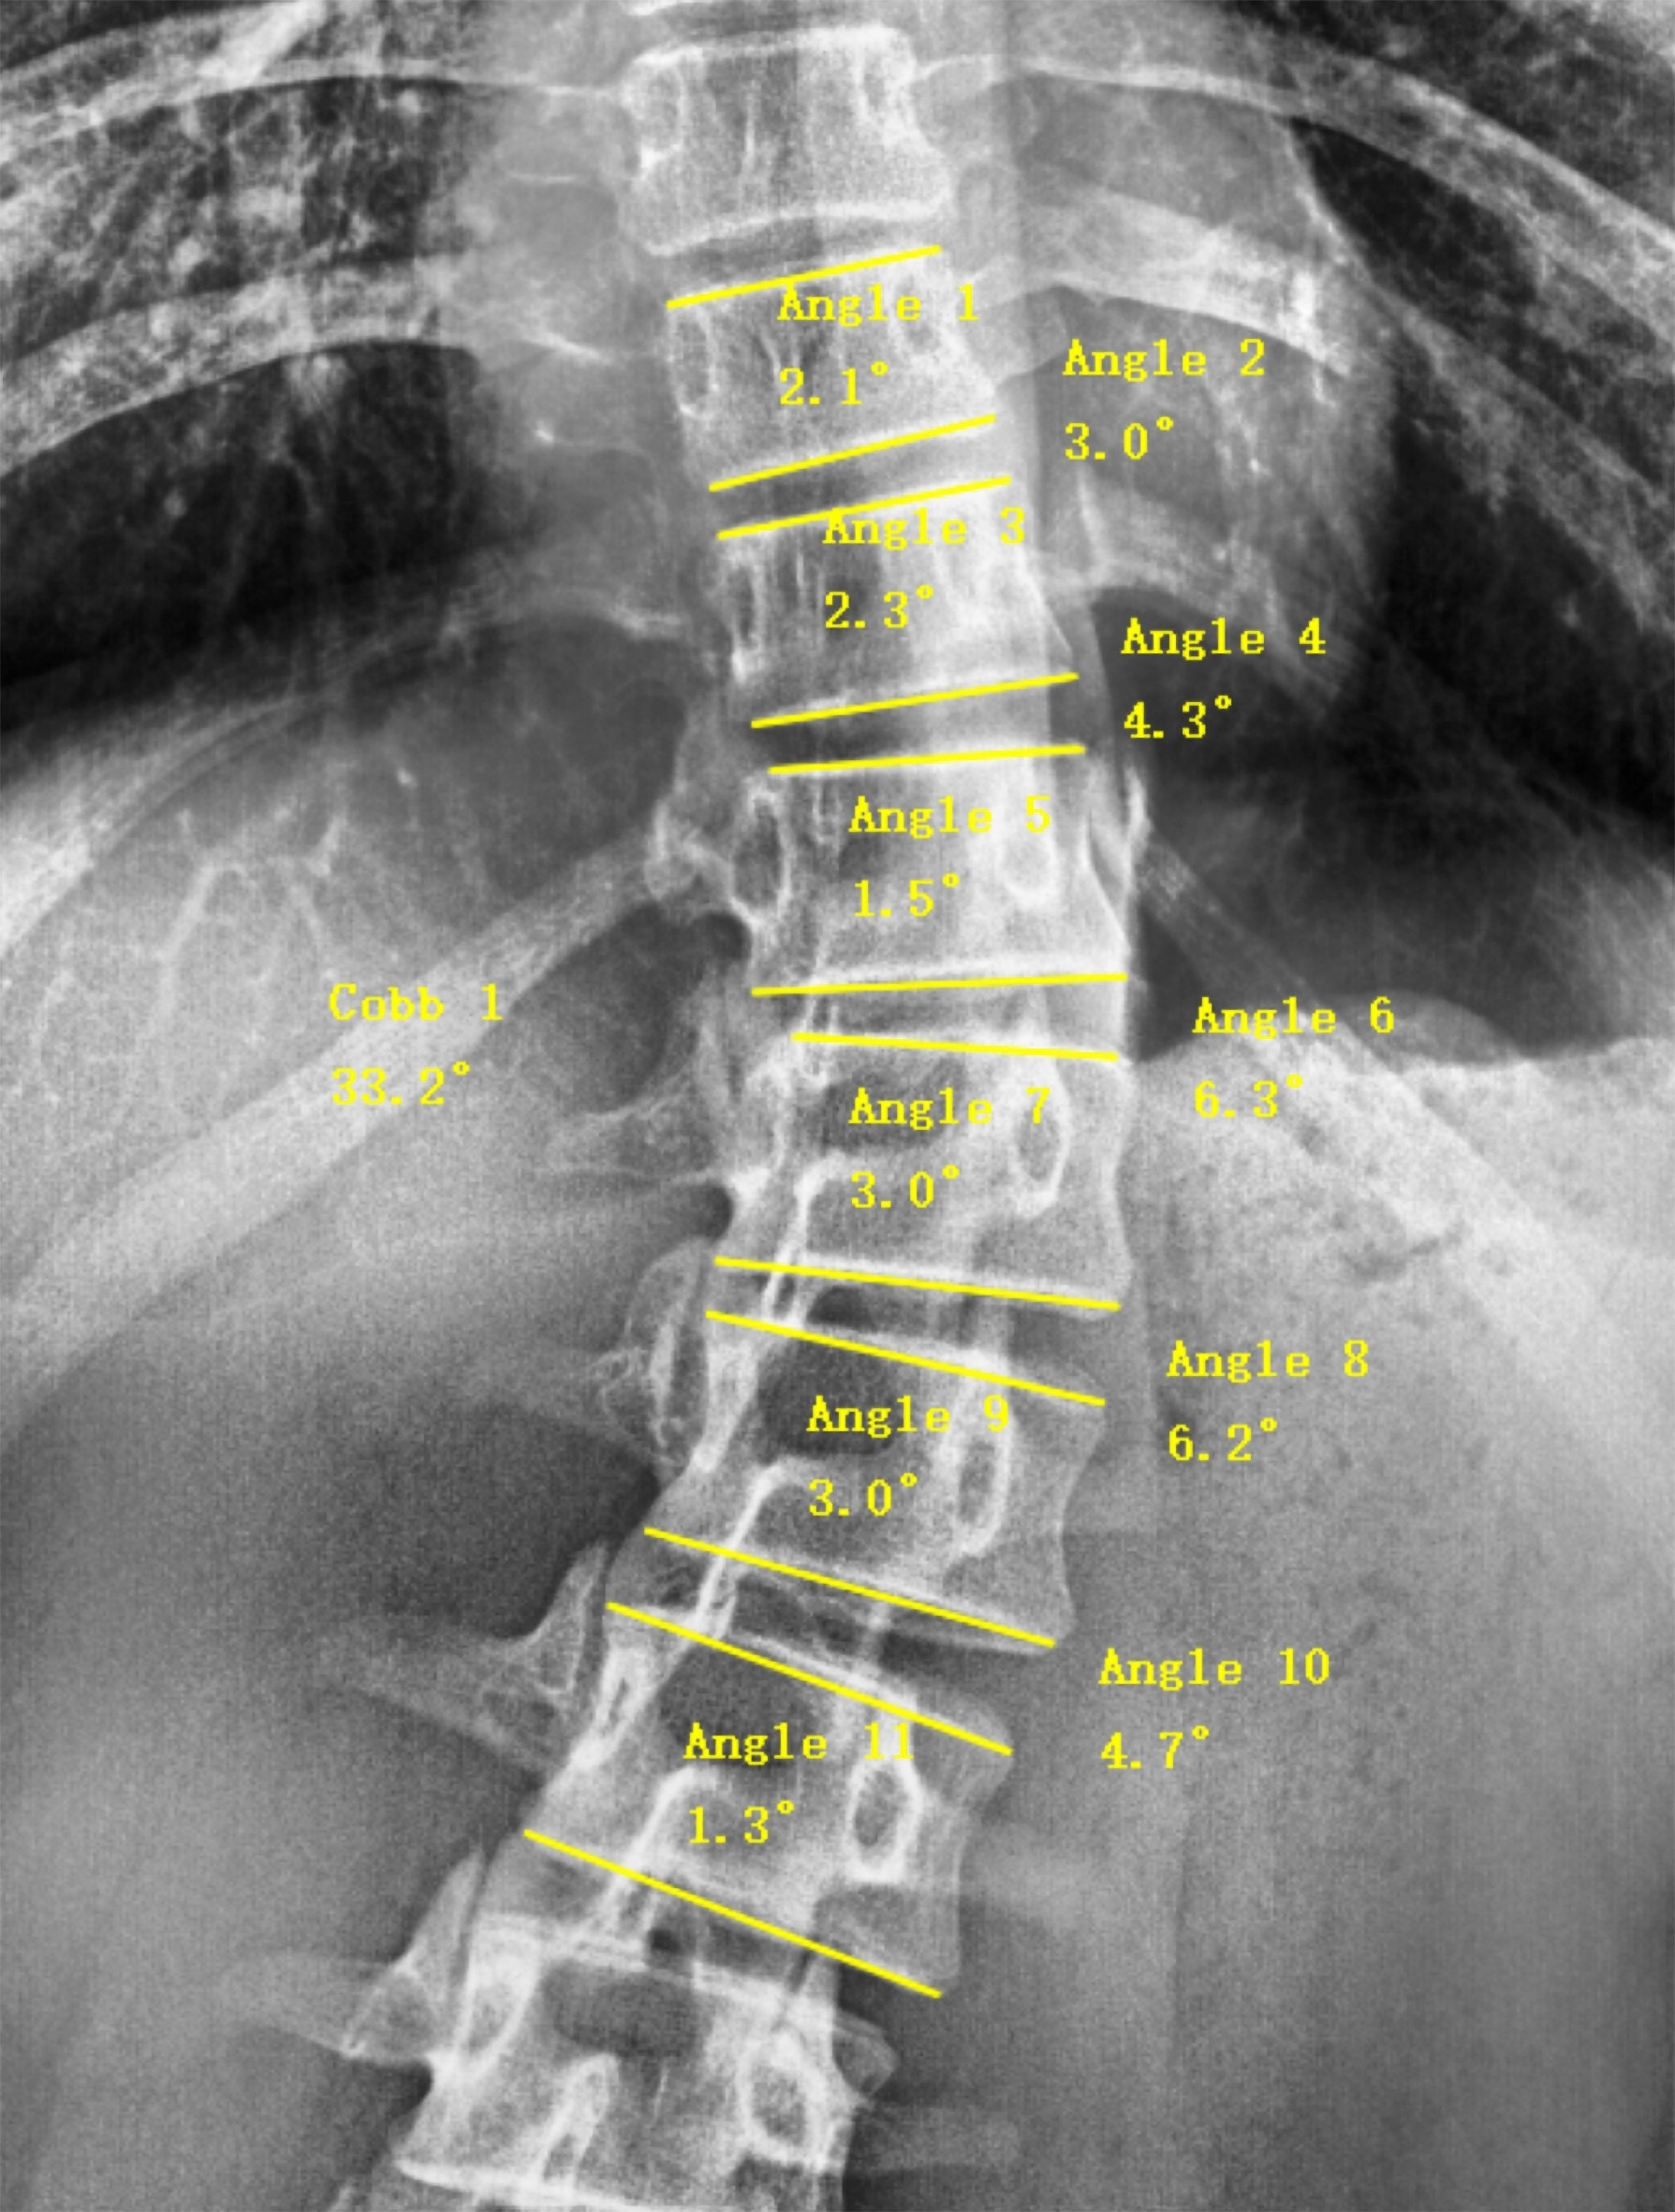

Surgimap software measurement for Cobb angle and wedge angle.